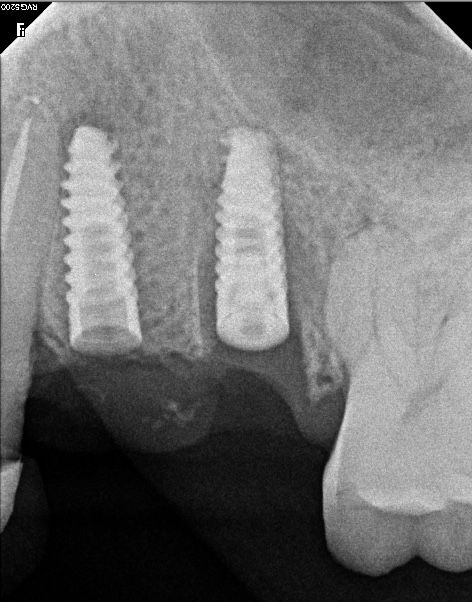

Especialista en Implantología Oral quirúrgica y protesica, cédula de especialidad: 12411844

La especialidad en Implantología Oral se enfoca en sustituir órganos dentarios perdidos por implantes dentales mediante una fase quirúrgica y una fase protesica y de esta manera devolver la función, estetica y confort dental del paciente.

• Implantología dental